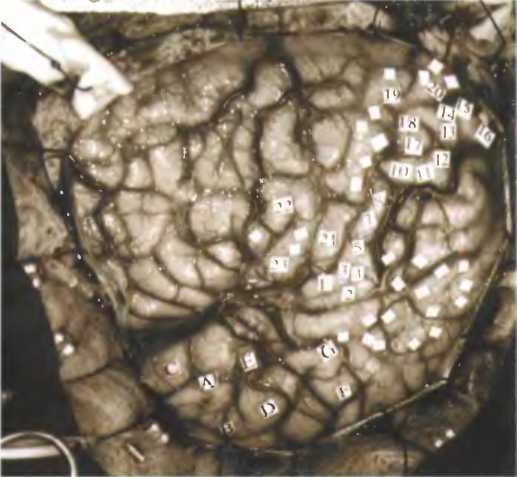

Канадский нейрохирург Уайлдер Пенфилд идентифицировал участки мозга, ответственные за воспоминания, стимулируя кору больших полушарий во время операций на головном мозге пациентов, страдавших эпилепсией. Пациент при этом оставался в сознании. Номерами отмечены места, стимуляция которых вызывала воспоминания.